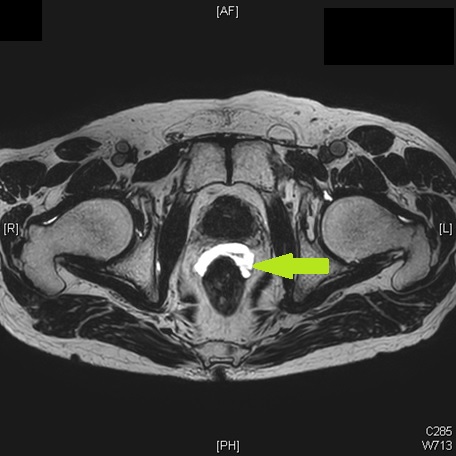

また、2019年からはスペーサーゲル(spaceOARⓇ)も導入して直腸の有害事象の軽減をはかっています。

スペーサゲル